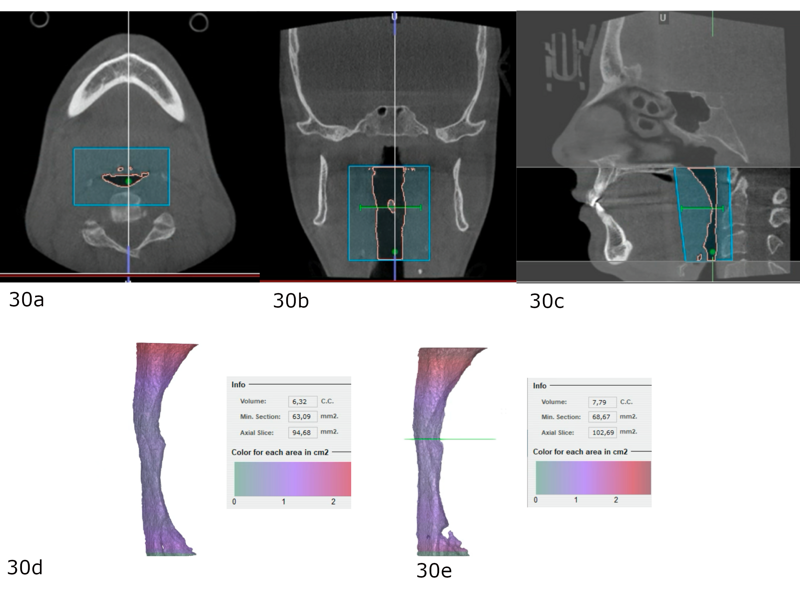

The final dental panoramic tomogram showed the correct levelling of the occlusal planes and root positions (Fig. 26). The final cephalometric tracing showed closure of the facial angle thanks to the posterior intrusion and mandibular auto-rotation (Figs. 27 & 28). Mandibular antero-rotation shortens the lower facial third, improving lip competence and ultimately the facial profile. The CBCT images of the TMJs showed the correct position of the condyles within the glenoid fossae (Fig. 29). When looking at the airway on the CBCT scan, we also saw an improvement of the patient’s airway (Fig. 30).

After treatment, the patient had bilateral Class I molar and canine relationships, correct overjet and overbite, centred midlines and improved arch forms (Fig. 52). Extra-orally, she had improved arch forms, a wider smile, an improved smile line and less gingival exposure (Fig. 53). The lower facial third had been shortened thanks to mandibular antero-rotation, and there was improvement of the upper lip support thanks to the positive torque of the maxillary incisors. In the post-treatment panoramic radiograph, we observed excellent periodontal status, no resorption of the roots and extraction of the maxillary third molars (Fig. 54). In the post-treatment cephalometric tracing, we saw a decrease of the ANB angle, a reduction in the anterior face height, an increase of the facial axis angle, and a decrease in the distance between the soft pogonion and the true vertical line thanks to the anticlockwise rotation of the mandible (Fig. 54). We also found an increase in the inclination of the maxillary incisors and an improvement in the final inter-incisal angle. Concerning her TMJs, the patient remained totally asymptomatic and had a vertical masticatory pattern and a stable arc of closure. The CBCT scan showed well-corticated condyles in the same position as that obtained after the splint therapy (Fig. 56).